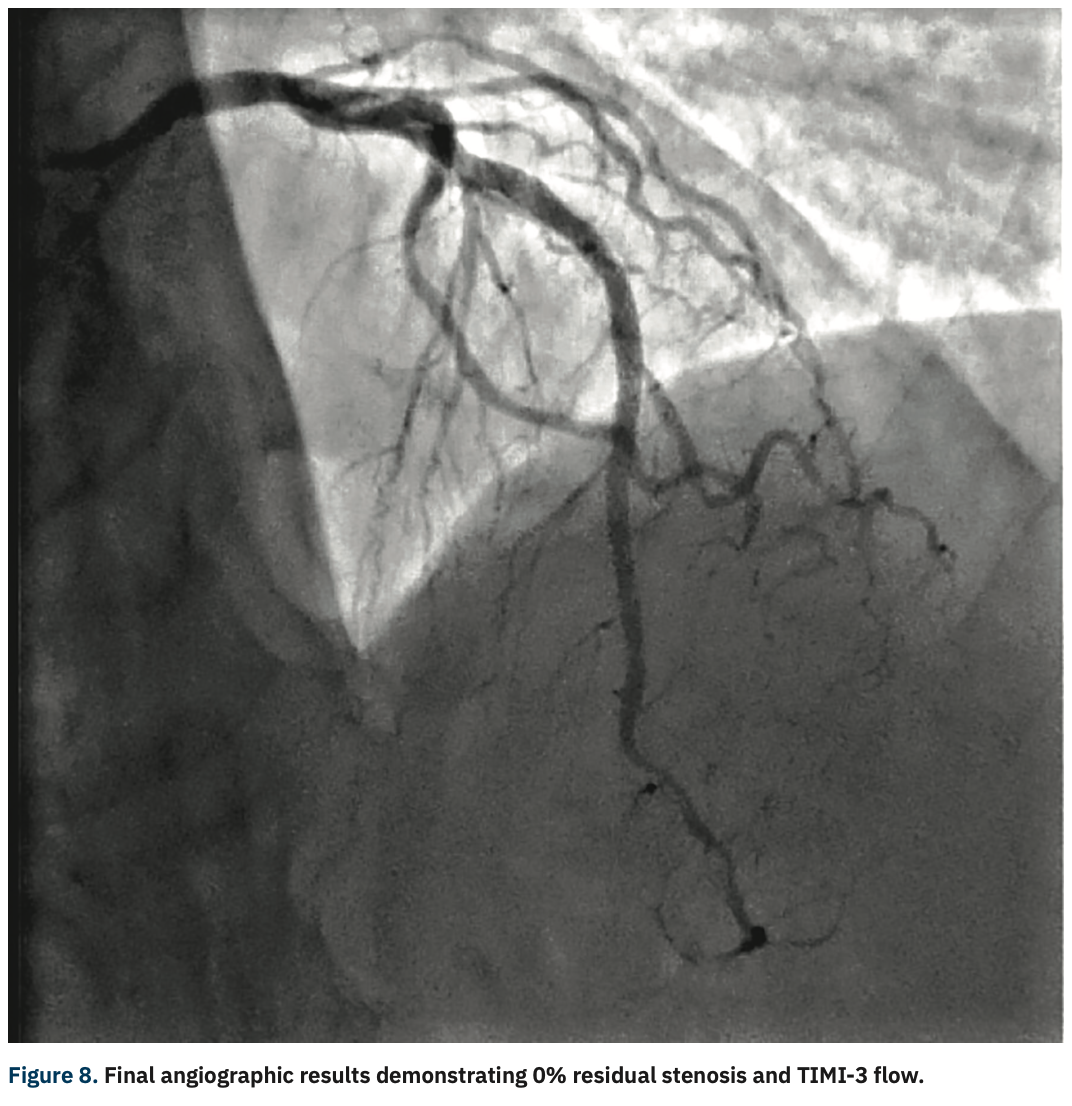

Like all centers, we are using more and more advanced imaging, but it is not uncommon for a lesion to be unpredictably difficult to dilate and more heavily calcified than is readily apparent on angiography. In those situations, with a lesion that will not dilate, it is necessary to have a method by which to modify the calcium, even though its presence was not anticipated. This is a particularly precarious situation for operators in non-backup settings. In the past, we would use oversized, non-compliant balloons and take them to very high pressures trying to achieve an adequate final stent result. In exceptionally rare cases, a handful of times over my 10 years here, we would even abort the case mid angioplasty and have to transfer the patient in a less than entirely stable fashion to the high-risk center. Calcium was our Achilles’ heel. We could always filter out the obviously high-risk cases, but there will always be a very small fraction of cases that do not have readily apparent calcium and are non-dilatable. IVL, from a safety standpoint, has been a game-changer for us not only in these cases, but also for cases with readily apparent calcium that otherwise would have required atherectomy. With the use of IVL, we are now at a point where the only cases that we have to either transfer or stage are non-crossable lesions: cases where you can get a wire but not a balloon across, and these are fairly rare.

With the ability to more aggressively treat calcium here at our primary site with IVL, there has been a big uptick in our utilization of intervascular imaging such as intravascular ultrasound (IVUS). We are bringing in optical coherence tomography (OCT), with the idea that we will image a much higher fraction of our cases, because of this concept of unappreciated calcification. When we see either moderate or worse calcium, or have a recalcitrant lesion or lesion that is not dilating normally, we are quick to pull the IVUS imaging catheter out in order to assess the arc, length, and width of the calcium. Post IVL, we will generally reassess the lesion to confirm fracture of the calcium. We don’t require IVUS post IVL for stenting, but it definitely is something that makes us feel good about moving forward with stent implantation. More and more, intravascular imaging is going to be a marketable quality indicator. If you are only doing a small percentage of intravascular imaging, I think you are going to be perceived as a lesser quality program. There has been a longstanding resistance to adopting a higher utilization of intravascular imaging, because of the combination of cost and time. I wish that CMS would see the benefit and create a situation where there are not negative financial incentives to doing imaging.

Yes. IVL turns a difficult PCI into an easy PCI with a device that’s easy to use and financially viable for the hospital. The safety issue can’t be overemphasized. Cases that previously required the use of buddy wires, and secondary and tertiary balloons, add time and complexity. Balloon ruptures are also more frequent. You then have to use new balloons and the chance of having a complication such as a perforation goes up. All it takes is one perforation where you have to do a pericardiocentesis and salvage an emergency situation to see the value proposition of IVL. The cost of ambulance transfers and the cost of all the additional ancillary staff for a secondary procedure is also immense. Optimal procedural results also reduce readmission rates, which brings cost savings and quality improvement in terms of outcomes. IVL is a win across the board, for patients, providers, and administration.